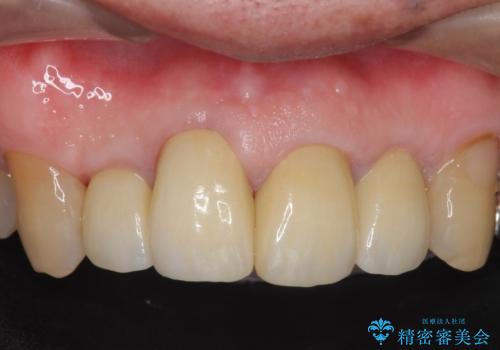

再根管治療後、オールセラミッククラウンによる補綴を行いました。

今回用いたオールセラミッククラウンは、ジルコニアフレームという白い素材の上にセラミックを盛っているため審美性が非常に高いのが特徴です。

またジルコニアは人工ダイヤモンドの材料にも使われているほど高い強度を持っており、そのためオールセラミッククラウンは審美性だけでなく、奥歯やブリッジの補綴も可能とするクラウンです。